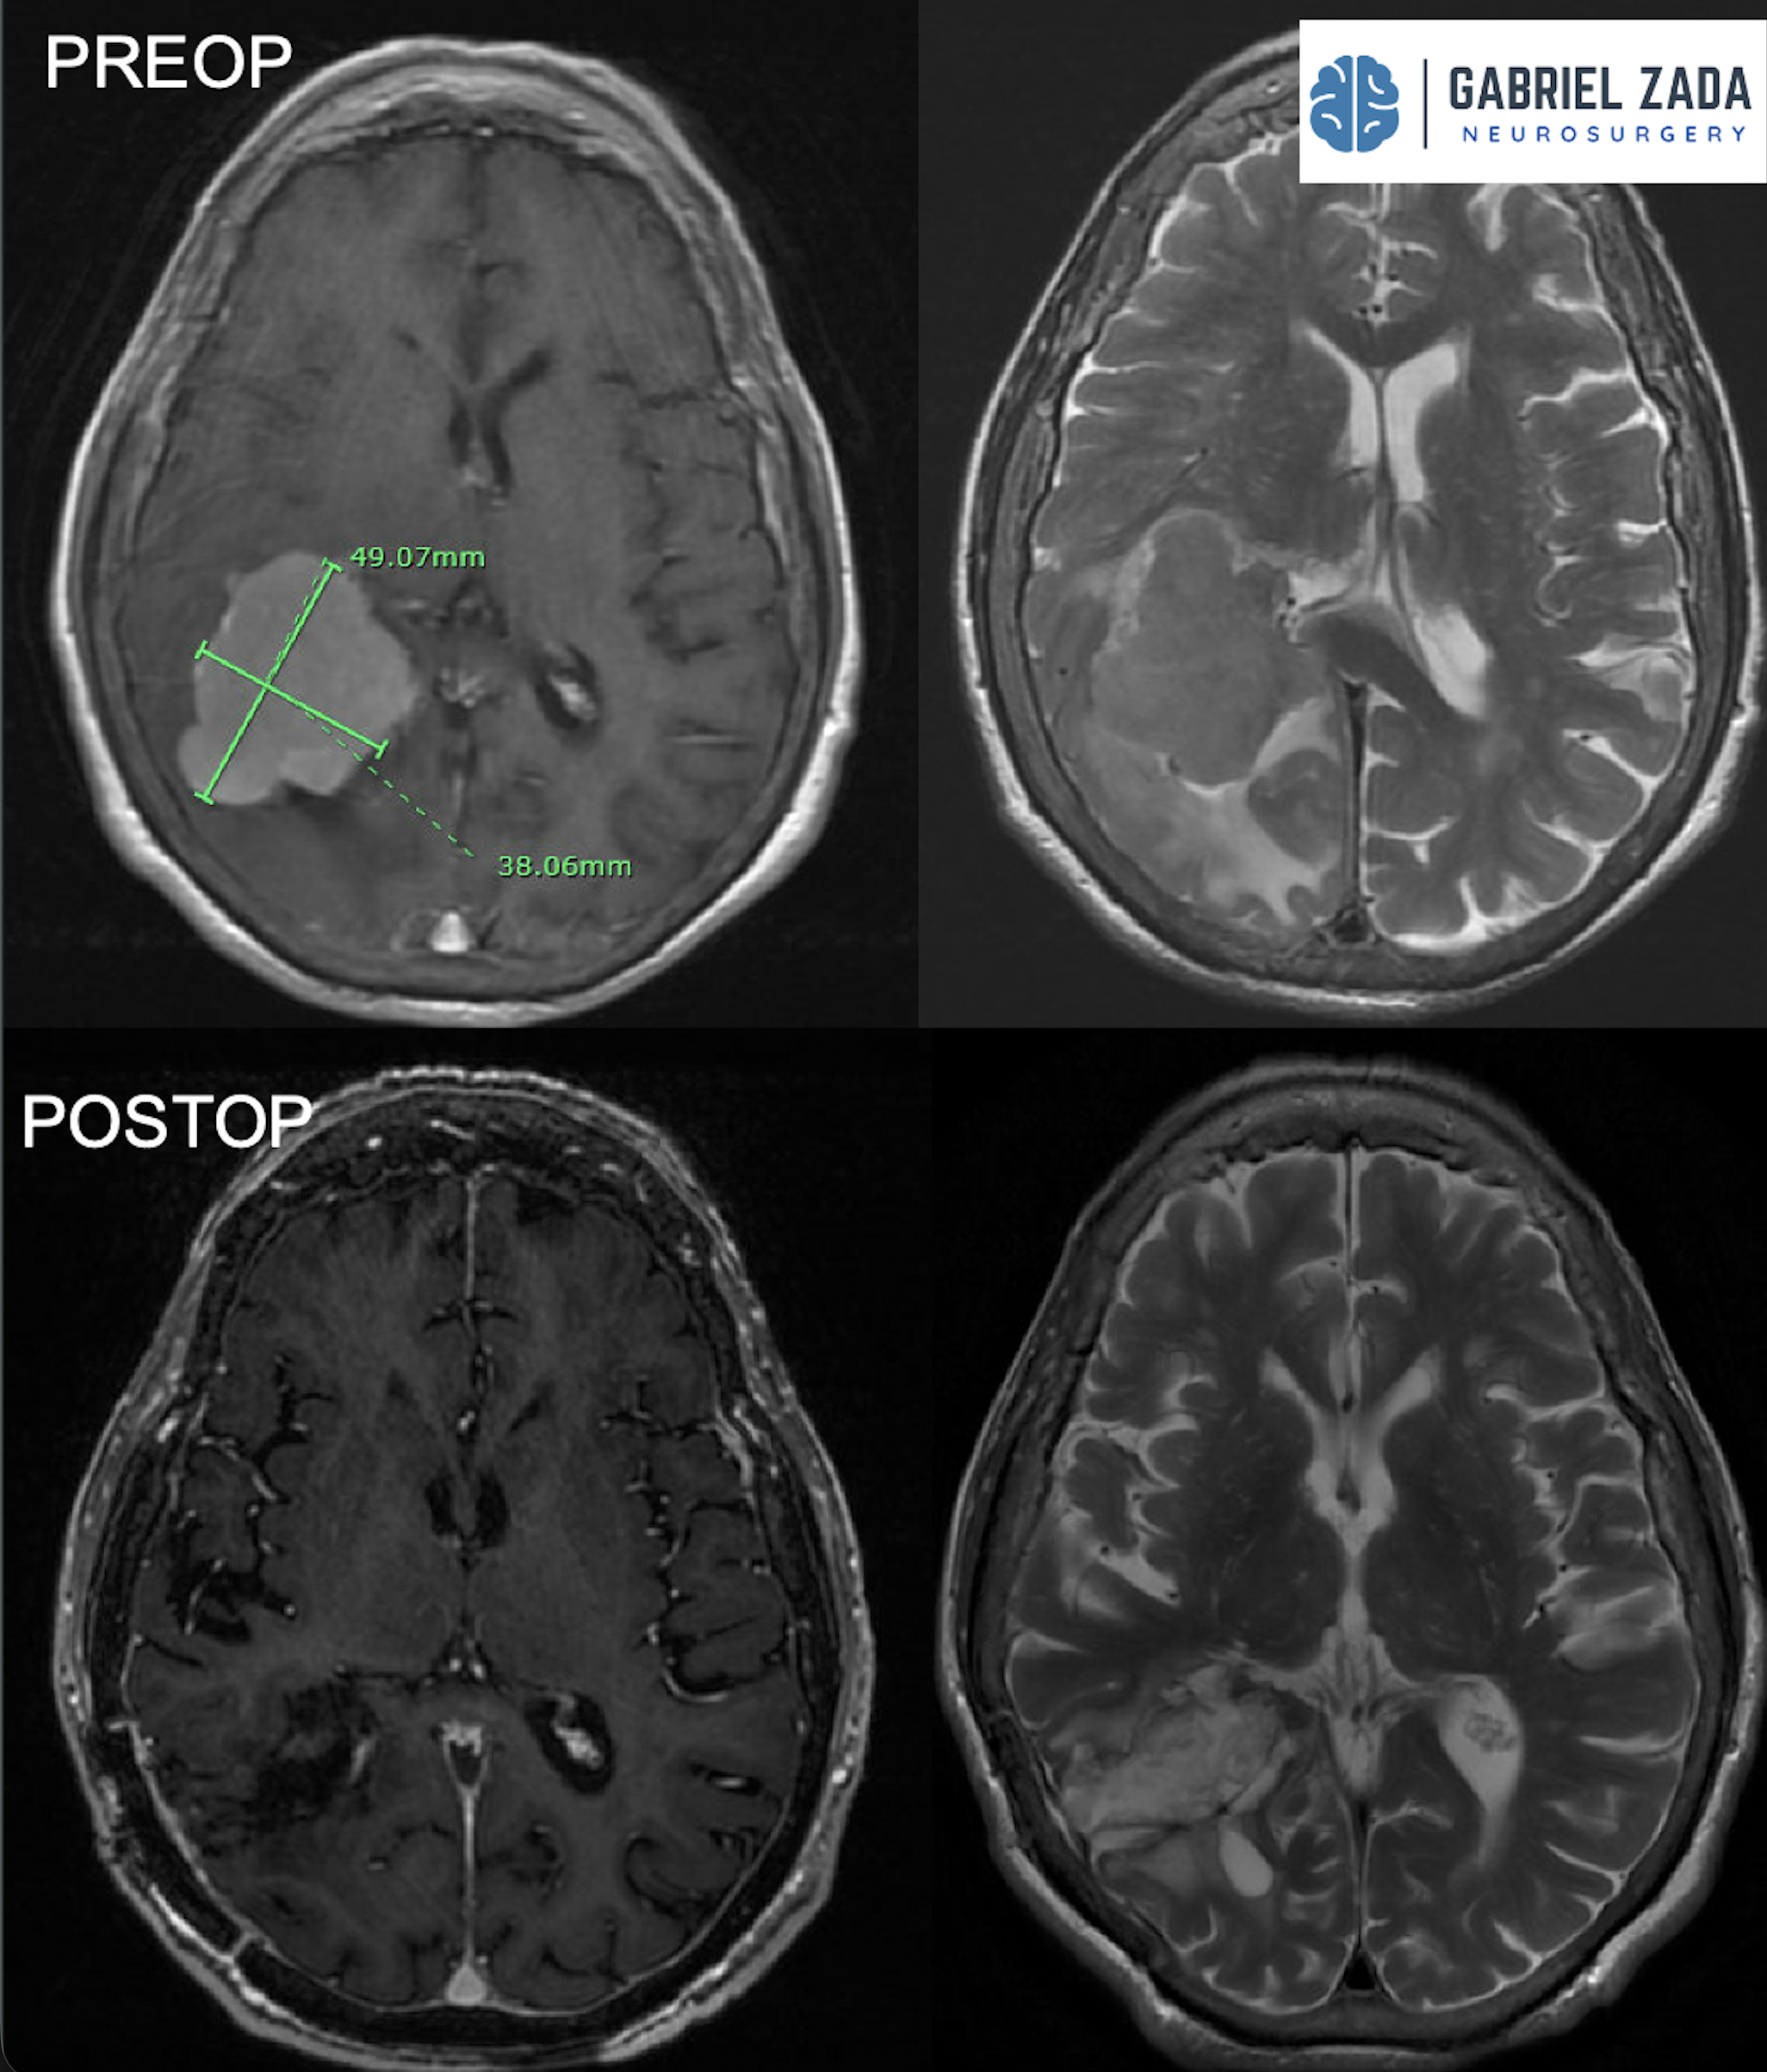

Explore this comprehensive gallery featuring pre‑ and post‑operative imaging of patients with skull‑base tumors treated by Gabriel Zada, MD, MS, FAANS, FACS. These cases highlight Dr. Zada’s expertise in advanced neurosurgical techniques and outcomes.

*Representative cases shown for educational purposes. All images de-identified. Individual results vary.